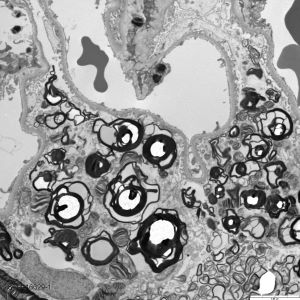

Renal biopsy laboratory, a sub-section of the main histopathology lab, receives approximately 850 renal biopsies per year from nephrologists at UAB and across the state of Alabama, with a broad spectrum of native and transplant cases.